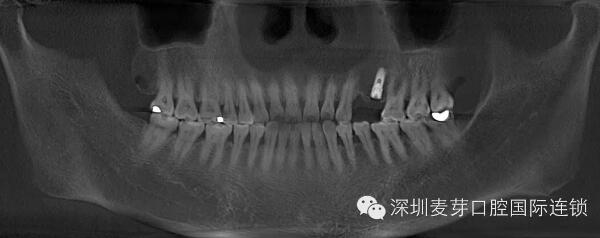

赵女士种植牙前后德国KAVO CT效果对比